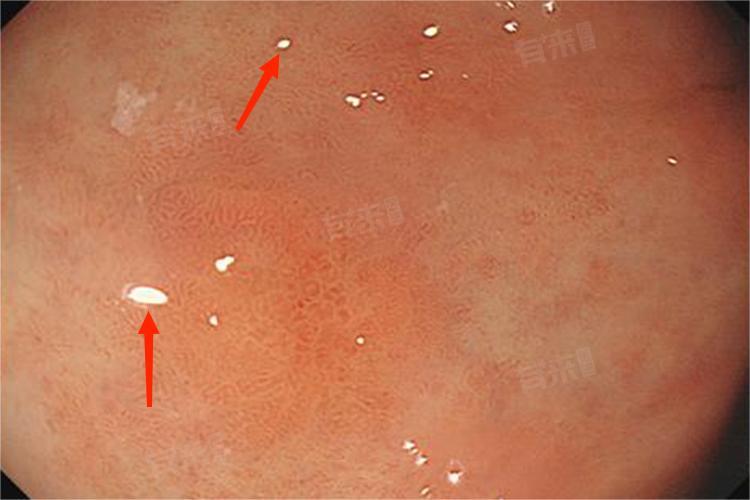

- 当发展至中度肠上皮化生阶段,在显微镜下可观察到胃黏膜组织中,肠型上皮细胞的占比已达到一定程度,超过轻度肠上皮化生时的比例,但尚未达到重度阶段的广泛程度。

- 肠型上皮细胞与胃黏膜上皮细胞在形态和功能上存在差异,它们更适应肠道环境,在胃内出现后,会干扰胃黏膜正常的屏障功能、分泌功能等。这不仅降低了胃黏膜对胃酸、胃蛋白酶等自身消化液的抵御能力,还可能影响胃内正常的消化和吸收过程。